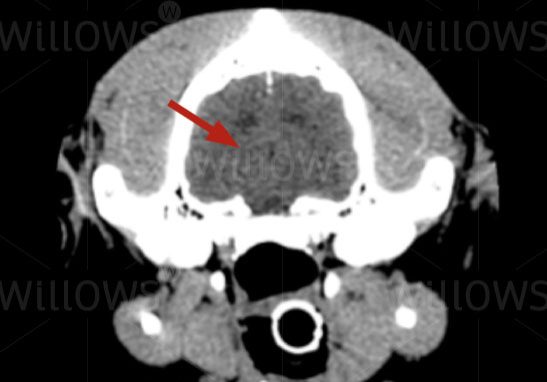

CT scan of a brain (arrow), again showing much less detail than the MRI scan. This view is a cross-section seen from the back (the skull around the brain is shown as bright white)